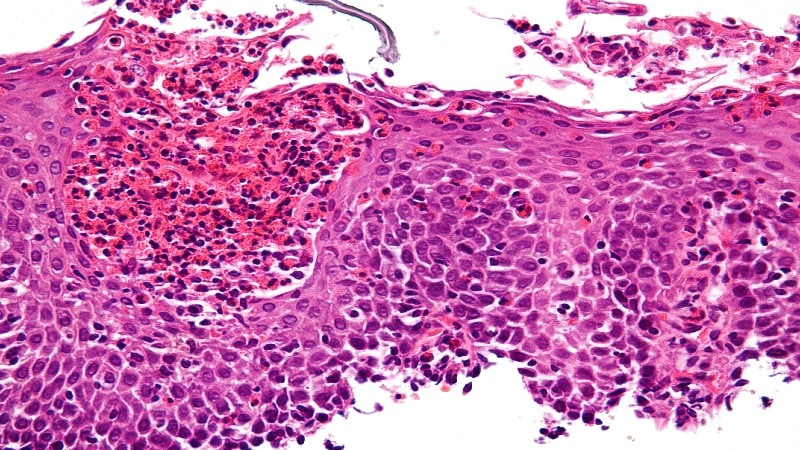

Las vacunas contra el virus del papiloma humano han tenido impacto drástico en el cáncer de cuello uterino -